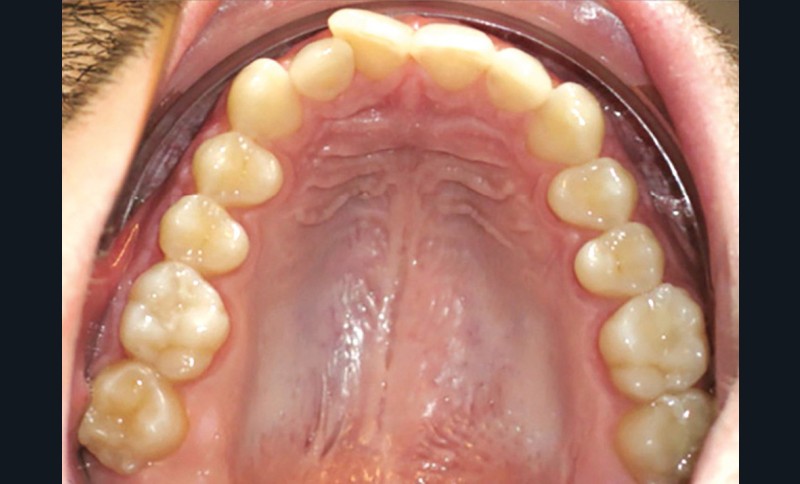

Examen endobuccal (fig. 2a-e)

L’arcade maxillaire est asymétrique, en hémi-lyre droite. Elle présente une mésio-position du secteur 1 en lien avec un encombrement antérieur estimé à 4 mm, se traduisant par une palato-position de la 12 et une rotation de la 11. On observe également des mésio-rotations des premières molaires et une palato-version incisive. L’arcade mandibulaire est ellipsoïde et présente un léger encombrement incisif (1 mm).

Concernant les relations occlusales, on observe une classe II complète subdivision droite. Le surplomb est absent et le recouvrement augmenté, estimé à 4 mm, a provoqué une usure des bords libres de 11 et 21 par attrition. Dans la dimension transversale, on constate une endoalvéolie maxillaire, ainsi qu’une concordance des médianes incisives entre elles, mais toutes deux déviées à droite par rapport au plan sagittal médian.